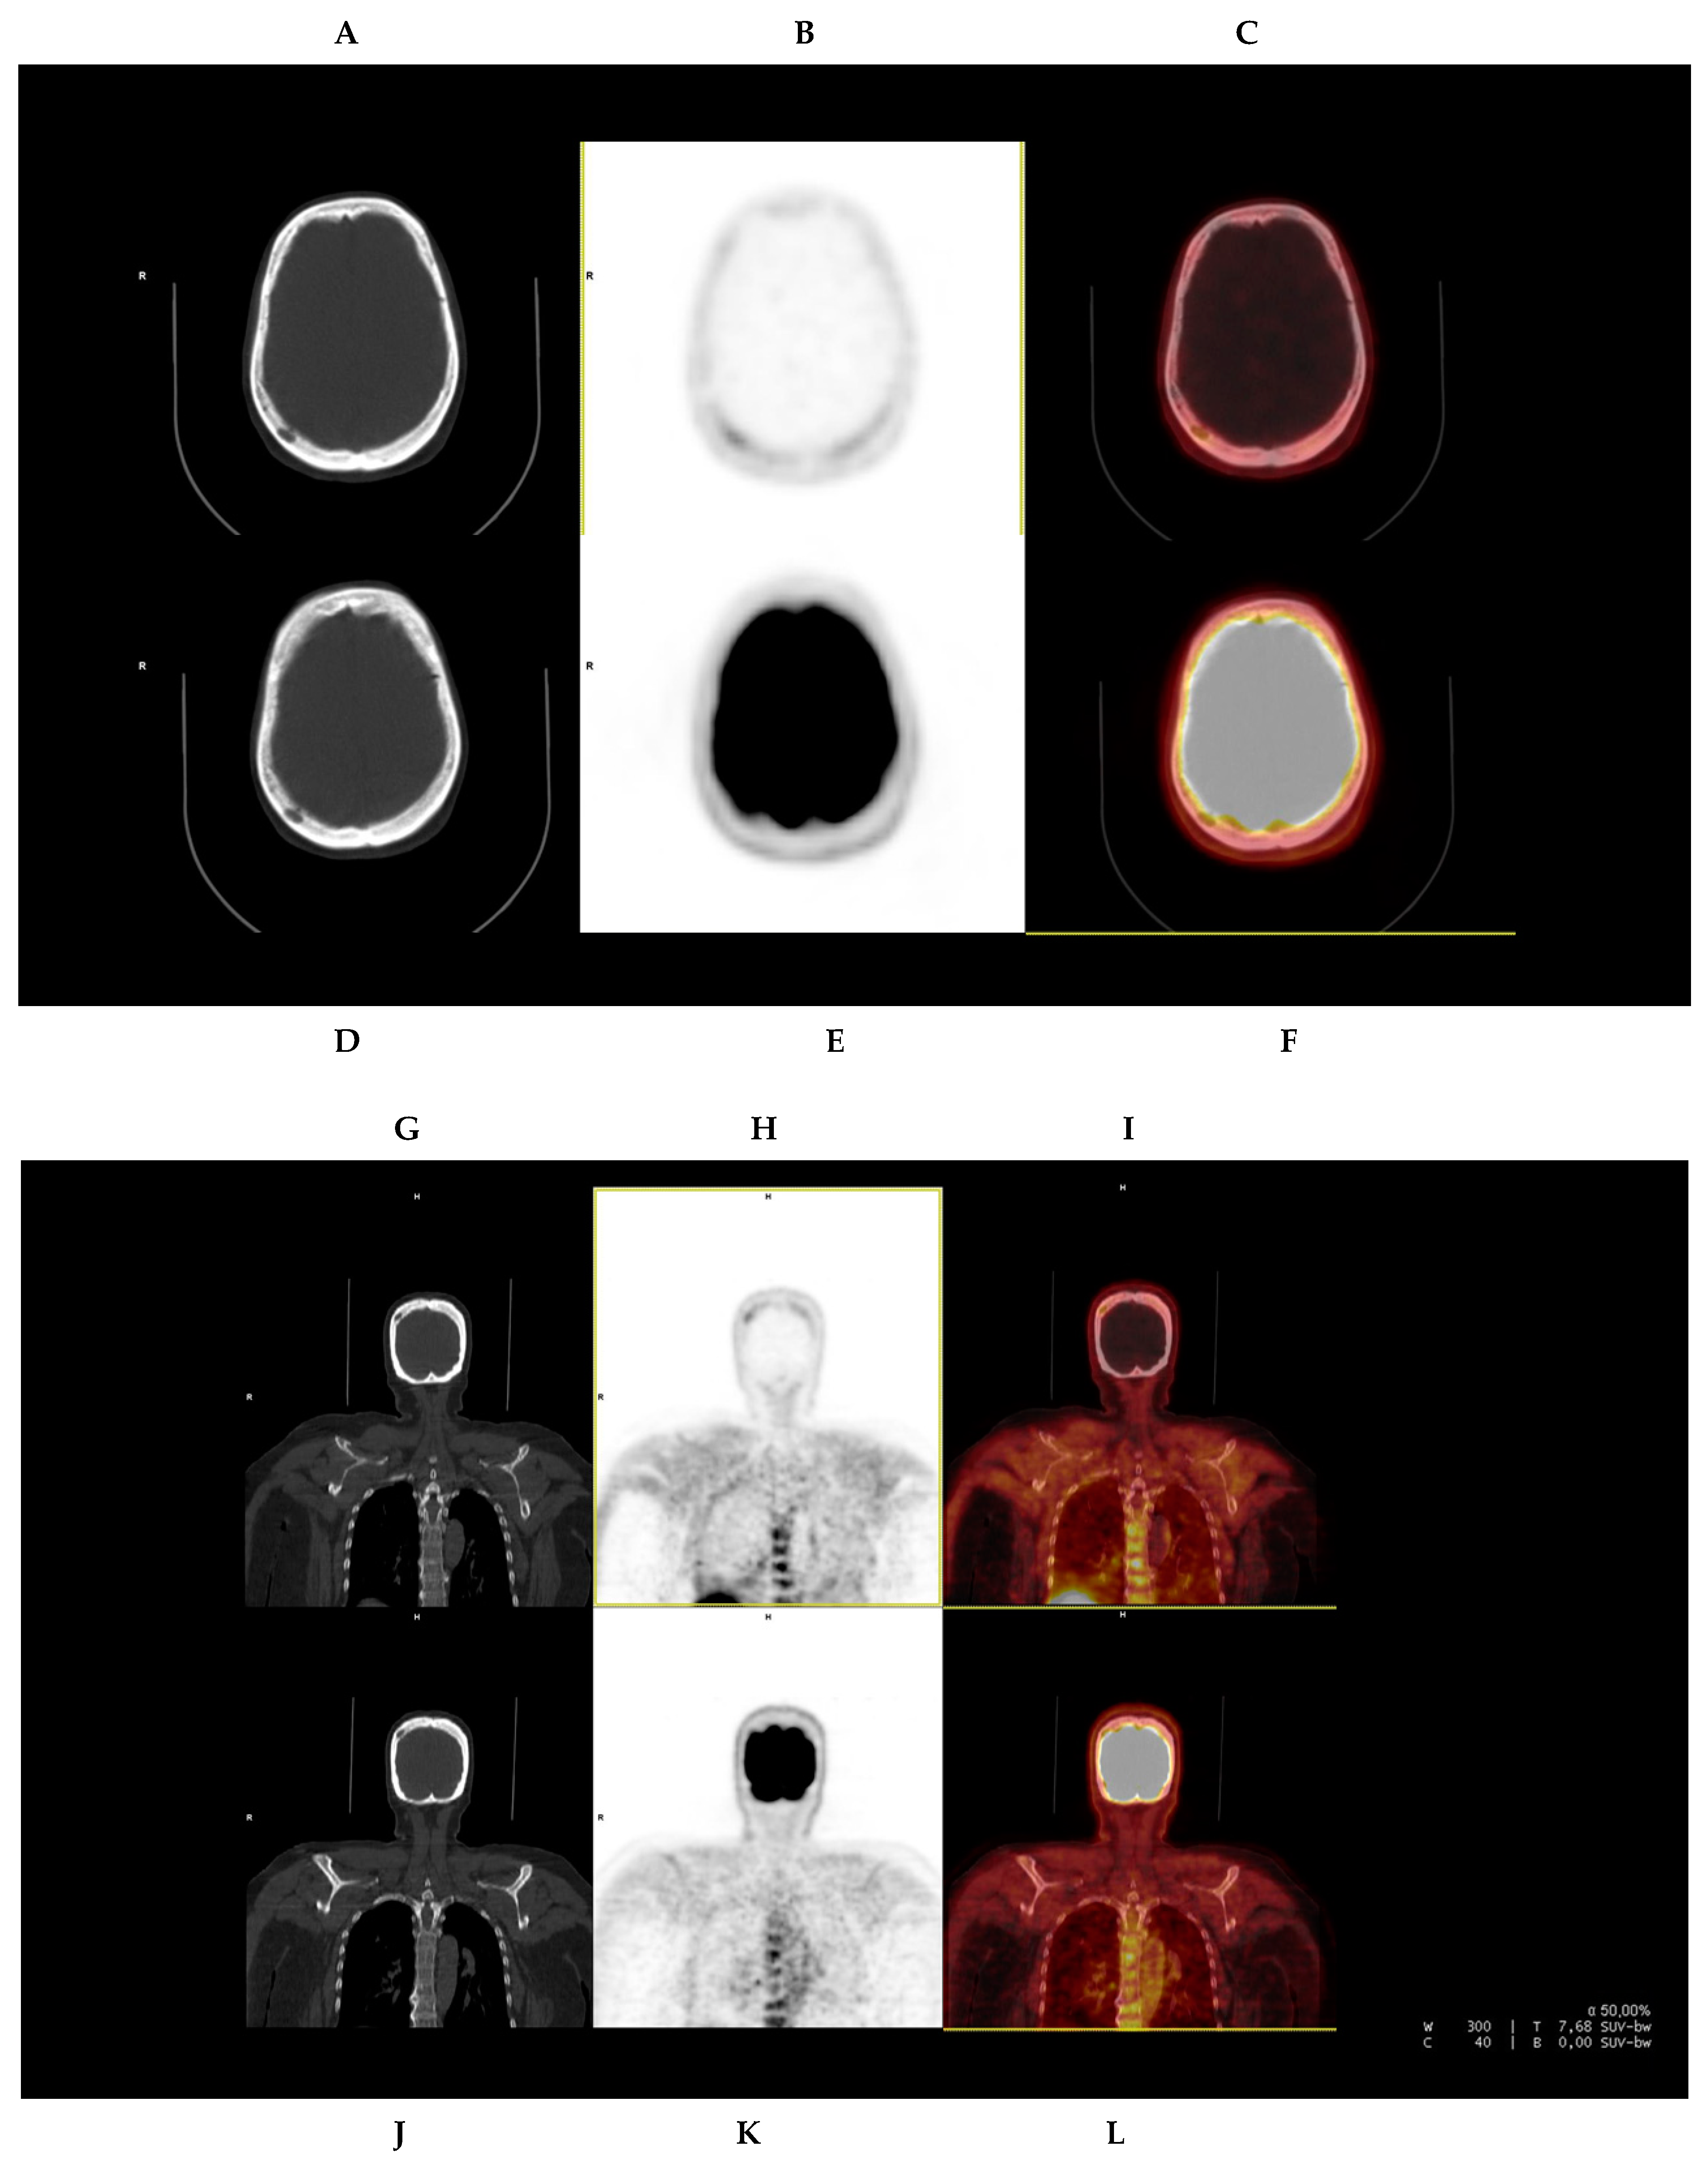

| 1 | No | Yes | No | Yes (1) | No | No | No | No | - | 4.3 (left iliac) | 2 | 3 |

| 2 | No | Yes | Yes (2) * | Yes (2) | Vagina and liver foci | No | No | No | - | 4.6 (D7) | 4 | 3 |

| 3 | Yes | Yes | Yes (1) † | Yes (1) † | - | - | Yes (1) | Yes (1) | 4.5 | 4.1 | 4 | 3 |

| 4 | No | Yes | No | No | - | - | Yes (1) | Yes (1) | 3.3 (lytic lesion) | 2.1 (lytic lesion) | 2 | 2 |

| 5 | No | Yes (patchy) | No | No | No | No | No | No | - | - | 3 | 3 |

| 6 | Yes | Yes | No | Yes (3) | Parotid adenopathy | Yes (1) | Yes (1) | Yes (1) | - | 7 (D5) | 3 | 3 |

| 7 | Yes | Yes | Yes (1) # | Yes (7) | Yes (1 PMD) | Yes (1 PMD) | Yes (2) § | Yes (5) § | 6.9 (left sacrum) | 8.9 (left sacrum) | 4 | 3 |

| 8 | No | Yes | No | No | - | Preauricular adenopathy | No | No | - | 2.7 (adenopathy) | 3 | 3 |

| 9 | Yes | Yes | Yes (4) | Yes (7) | Yes (1, rib PMD) | Yes (1, rib PMD) | No | No | 4.6 (D9) | 6.3 (D9) | 4 | 3 |

| 10 | Yes | yes | Yes (>10) | Yes (>10) | No | No | Yes (>10) | Yes (>10) | 5 | 3 | ||